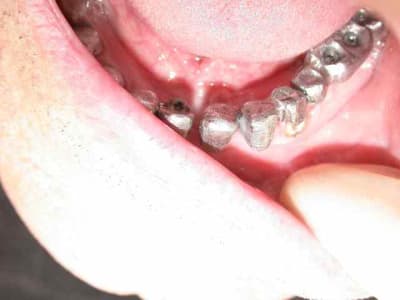

bridge transvissé sur 37 36 35 scellé sur fm implantaire sur 32 31 .

couronnes unitaires sur 42 41 (41 mal située position un peu trop lingual : la vue linguale de la photo montre notre solution prothétique pour l'axe)

bridge dentoporté sur 47 46 44 43

pano et photos a suivre les photos sont pas tops car vieil apparei et je vous le rappelle (reflex nauseeux,faut pas aller chercher trop loin quand même , mais vous verrez à la fin on met des écarteurs photos si si...)